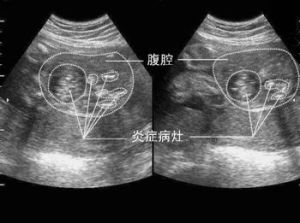

胎糞性腹膜炎腹腔鈣化當胎糞在迴腸里變硬並造成阻塞的病徵,被稱為胎糞性腸阻塞(meconiumileus)。胎糞性腸阻塞經常都是囊腫性纖維化(cysticfibrosis)的早期症狀。若胎兒患有囊腫性纖維化,胎糞會在迴腸內形成一種瀝青狀的墨綠色腸段阻塞。除此之外,有時胎糞還會形成一種灰白色小石狀的結物。在阻塞段落以下的腸道既窄又空。在阻塞部位以上,有多圈肥大的腸道,而且因為充滿了液體而變得膨脹。由於胎糞不能排出,嬰兒在出生後不久就會出現腹部腫脹及會嘔吐。